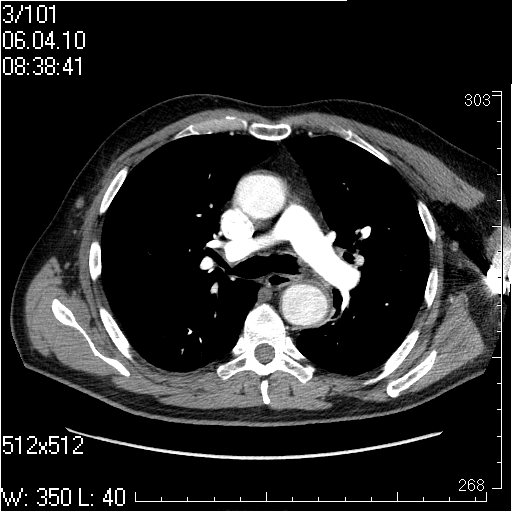

Грудной отдел аорты

Пожилой мужчина, жалоб в настоящее время не предъявляет.